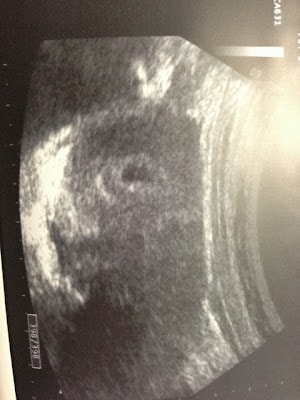

一大早就跑到東區幸福婦產科報到, 希望今天一定要照到胚胎啊啊啊啊啊啊啊~~ 在醫生左翻又找(?)後, 終於找到了小小小小的胚胎—

今天去了東區的”幸福婦產科”, 驗尿後, 醫生非常肯定的說 “有了喔!”我完全不意外地: “嗯。”醫生: 要照超音波看看嗎? 我: 好啊